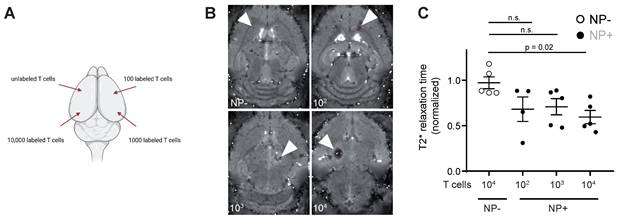

To assess the detection sensitivity of NP labeled T cells by MRI, different NP labeled T cell concentrations (unlabeled vs 102 - 104 NP+ T cells) were injected into the parenchyma of mouse brains ex vivo to identify the detection limit of labeled T cells (Figure 3A). 104 NP labeled T cells could be visually detected by T2* imaging and showed a significant shortening in T2* relaxation time compared to unlabeled T cells (Figure 3B). Therefore, the detection limit of NP labeled T cells by MRI in our approach is ~10.000 T cells.

Figure 3

A: Schematic visualization of the four intracranial T cell injection sites. Injections were performed with 10.000 unlabeled or NP+ T cells (100, 1.000 or 10.000 T cells) B: T2* images of intracranial T cell injections. Arrowheads indicate the injection site C: Quantification of T2* time of intracranial, iron oxide NP labeled T cell injections. Relaxation time was normalized to the adjacent healthy brain tissue